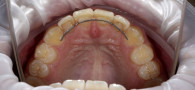

Пациентку 25 лет беспокоили скрученность и наклон зубов обеих челюстей. За помощью она обратилась к нам в клинику «Виртуоз».

Консультацию проводила врач-ортодонт Горяйнова Татьяна Сергеевна. После осмотра и диагностики доктор назначила ортодонтическое лечение, порекомендовав установку брекетов.

Ортодонтическое лечение длилось 18 месяцев. В результате зубы пациентки приняли правильное положение. Теперь девушка очень довольна своей улыбкой!

В период лечения пациентка носила брекеты, выполняла все рекомендации врача, следила за гигиеной зубов и ежемесячно приходила на корректировку в Центр стоматологии «Виртуоз». В конце лечения доктор назначила ношение ретейнеров для закрепления результата. Всего через полтора года зубы стали ровными и перестали доставлять девушке какой-либо дискомфорт.